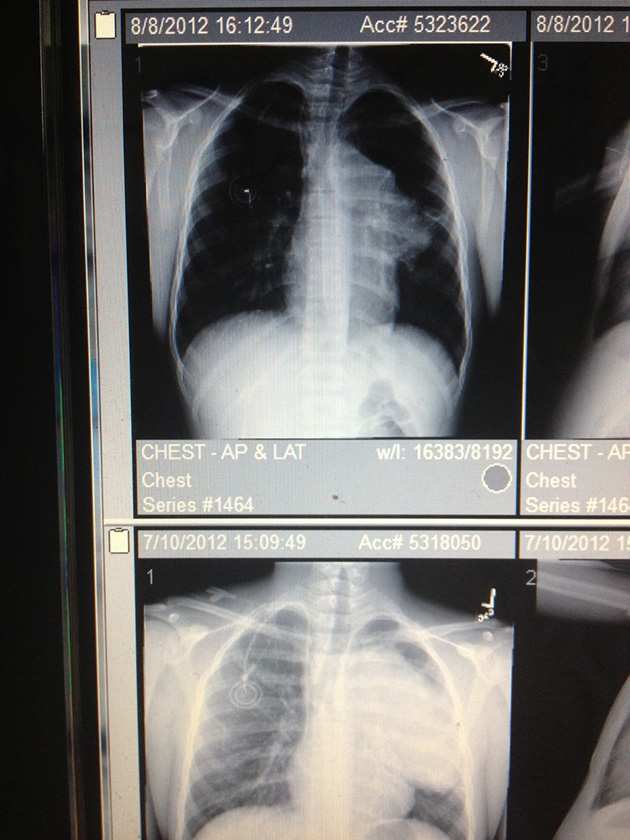

Above is a picture of two of Edler’s MRIs. The first one (bottom) shows an 11.5 centimeter long white mass (the tumor) taking over his right lung and pressing against his windpipe. The second one (top) shows a significantly smaller growth after his first 21-day cycle of chemotherapy.